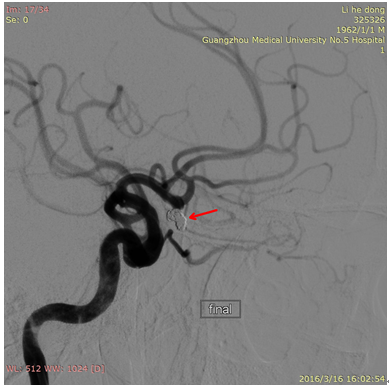

医生首先给李先生做了脑血管造影检查,如前所料,发现左侧前交通动脉瘤。神经内科张斌主任主持全科及神经外科张显强医师进行跨科室讨论,经积极的术前准备,决定急诊行颅内动脉瘤微弹簧圈介入栓塞术。介入手术在我院新引进的大型C臂飞利浦DSA机下完成。在张斌主任指导下,由张显强副主任医师主刀完成,术中发现动脉瘤约5mm大小,远端已形成破裂小泡,如不及时治疗,一旦再次破裂,后果不堪设想。经过1小时紧张的手术,在动脉瘤内填塞入4枚微弹簧圈,顺利结束手术。目前患者已康复出院,患者家属对治疗结果非常满意。

栓塞后的动脉瘤